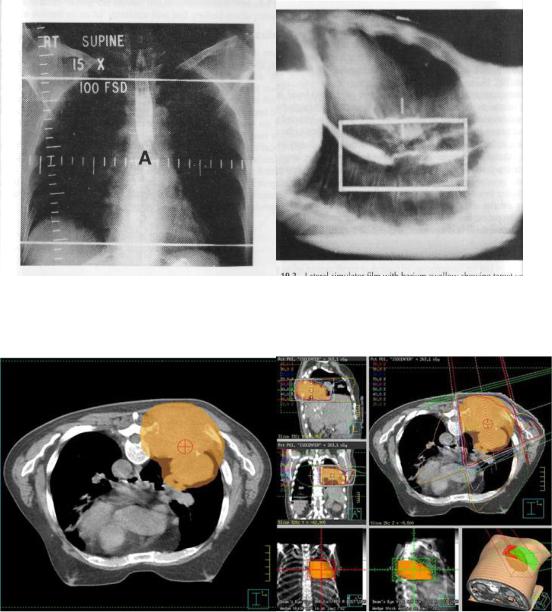

1.«Взгляд» на симуляторе с использованием низкодозных Rо-лучей или КТ и последующая установка коллиматоров в соответствии с контурами опухоли (применяются рентгеновские или КТ-симуляторы).

Это более простой, но более грубый вариант предлучевой подготовки

(рис.1)

2.Виртуальная симуляция (проводится с применением современных компьютерных томографов и соответствующего программного обеспечения, позволяющего в короткие сроки создать множество изображений опухоли в разных проекциях и определить облучаемые

объёмы с учётом индивидуальных особенностей (размеров, формы,

распространённости и т.д.) (рис.6).

Рис.6. Пример рентгеновской симуляции при раке пищевода.

Рис.7. Пример виртуальной симуляции при раке лёгкого.